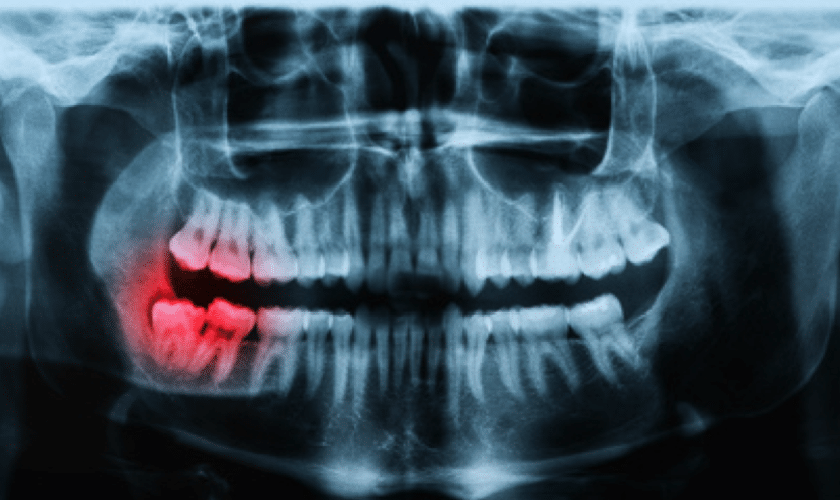

In this blog post, we’ll delve into the three main types of dental X-rays: bitewing, periapical, and panoramic X-rays. We’ll explore their purposes, procedures, and how they aid dentists in ensuring your oral health.

The X-ray machine for panoramic X-rays is different from those used for bitewing or periapical X-rays. You’ll stand and position your chin on a platform, with your head cradled comfortably. The machine will rotate around your head, capturing a panoramic image of your entire mouth in a single scan.

- Provides a broad view of your entire mouth and jaw structures in a single image.

- Helps identify potential problems that might not be apparent with other types of dental X-rays.

- Useful for planning complex dental procedures like implant placement or wisdom tooth extraction.

- Can aid in diagnosing jawbone abnormalities, TMJ issues, and other conditions affecting the facial structures.